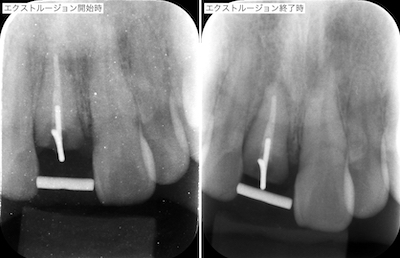

(前回までのあらすじ)仮歯作成し、ホームホワイトニングを行ったのち、歯の予知性を高めることと、歯肉のラインを審美的改善を求めるために、エクストルージョンを行うことになりました。

両隣在歯は切削していません。施術はきちんと行う上で、患者さんには審美的苦痛がないように努めました。1ヶ月程度で、予定の位置まで矯正的挺出させました。

エクストルージョン前後の歯肉です。

患者さんはホームホワイトニングの結果に満足しておられたのですが、歯肉縁上の残存歯質が少なすぎて、今後の安定性に不安があること、エクストルージョンを行えば、歯肉縁上の歯質を確保でき、予知性を高めることができて、歯肉のラインも改善できることを説明しました。